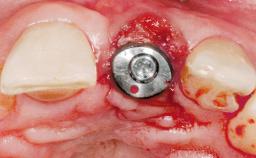

A 36-year-old female patient was referred for the replacement of the upper left central incisor (tooth 21), which had fractured. Although the tooth had been asymptomatic for many years, the crown began to loosen, at which time she presented to her dentist for an assessment. Teeth 21 and 22 had both been endodontically treated many years previously. She was a healthy individual and a non-smoker.

Placement Protocol | Early or late implant placement |

Bone Volume | Deficient horizontally, requiring prior grafting |